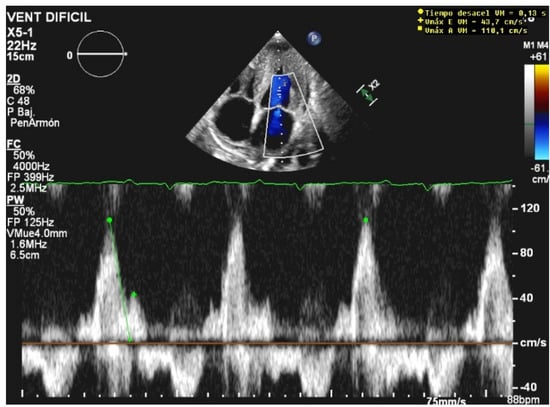

Unlike MV weaning assessment, evaluation of systolic function is the key factor in the decision to wean from ECMO. Weaning can be attempted when the ejection fraction of the left ventricle is higher than 35% and/or the left-ventricular outflow tract velocity time integral (VTI) is higher than 15 cm/s, with a minimal ECMO flow under 1.5 L/min or less than 1500 rpm [9]. Previous studies have also proposed lower values of both ejection fraction (around 20–25%) and VTI (10 cm/s) for a successful weaning [32,33] (Figure 3 and Figure 4).

Figure 4.

Pathological low left-ventricular outflow tract velocity integral (VTI).